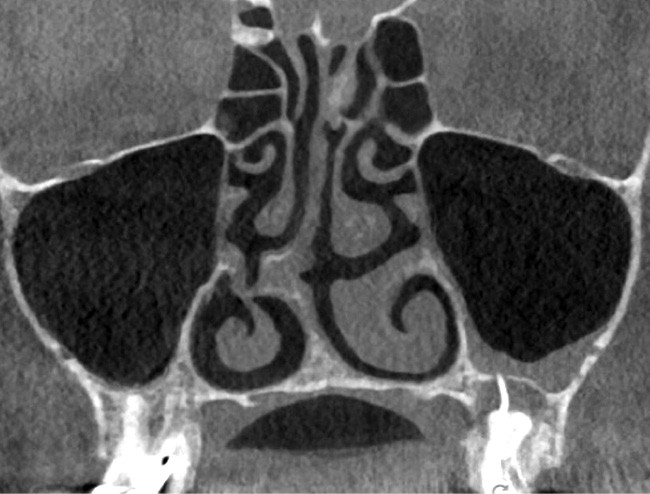

L’utilisation du scanner, et maintenant du CBCT, bouleverse l’idée très radiographique que nous avions du système canalaire.

Rebondissant sur l’imagerie 3D et la mise en évidence des anatomies canalaires complexes, Peters, en 2001, décrit l’insuffisance instrumentale dans le traitement endodontique, et montre que 35 % des surfaces sont intactes après préparation canalaire correctement menée [18].

Endal, en 2011, montrait également, en utilisant le micro CT Scanner, l’insuffisance de nettoyage des isthmes inter-canalaires à nos techniques conventionnelles [19]. L’utilisation du laser Er:YAG devenait alors incontournable dans le nettoyage de ces isthmes et des zones non instrumentées (fig. 2 et 3).

Si l’étude de Peters [18] nous montre que l’instrumentation laisse 35 % du volume canalaire non instrumenté, Ricucci et Siqueira montrent que la préparation physico-chimique n’élimine que partiellement les tissus nécrotiques à l’entrée des canaux latéraux, des isthmes et des ramifications apicales, en laissant des tissus enflammés et infectés, en association avec des lésions apicales [29] (fig. 4 et 5).

Si les isthmes sont particulièrement mis en évidence au niveau des molaires mandibulaires, cela devient médicalement important au niveau des molaires maxillaires.

La diffusion bactérienne et de leurs toxines, au niveau des molaires maxillaires est à l’origine d’un grand nombre de sinusites maxillaires chroniques, d’origine dentaire. Celles-ci sont principalement causées par l’absence de traitement du deuxième canal MV, qui existe dans 90 % des cas, et il est à noter que ces deux canaux – MV1 et MV2 – sont également reliés par un isthme.

Le nettoyage des isthmes intercanalaires reste un réel problème, et semble responsable de nombreux échecs [43]. Par ailleurs, il est nécessaire d’utiliser des instruments qui évitent de propulser les débris, tant apicalement que latéralement, en obturant les entrées isthmiques avec des débris compactés.